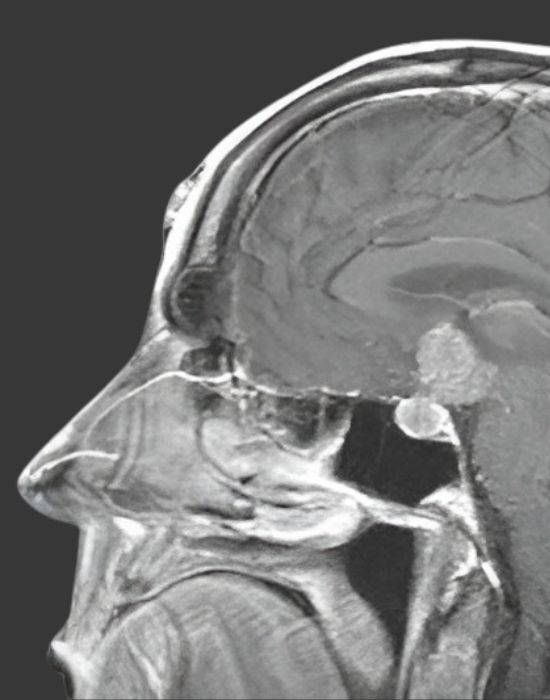

МРТ-діагностика гіпофіза та патології орбіт